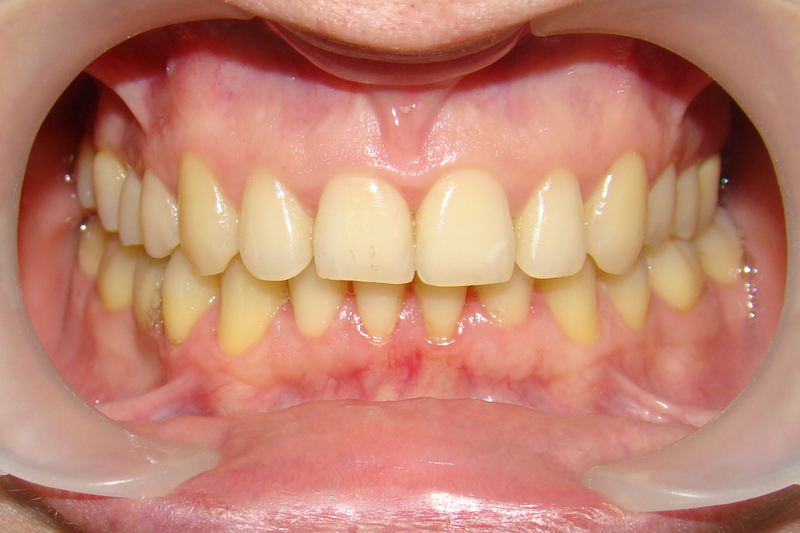

А это уже молодой человек 10 лет. Тоже получилось справиться без удаления. Хоть оно и было показано. Но мальчик очень упорно носил специальные аппаратики и резиночки. Покажу со всех сторон. Этот случай победил в конкурсе на конференции